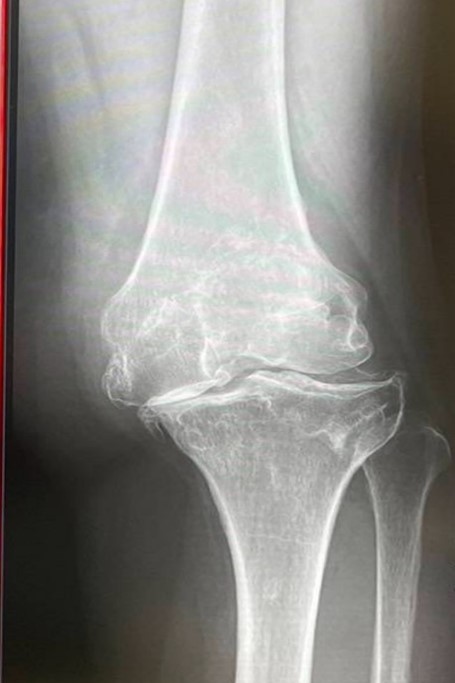

変形性膝関節による膝の痛み

加齢や体重の増加により軟骨組織がすり減っていき、膝を守るクッションが無くなってしまう為、膝同士がこすれあい関節痛が生じます。膝の内側が痛くなることが多いです。

女性に多くみられ、足がO脚であったり、また肥満が原因で発症することがあります。

症状に段階があり、最初は膝に違和感があるという所から始まり、段々常に痛むようになり、最終的に酷く痛むようになってきます。